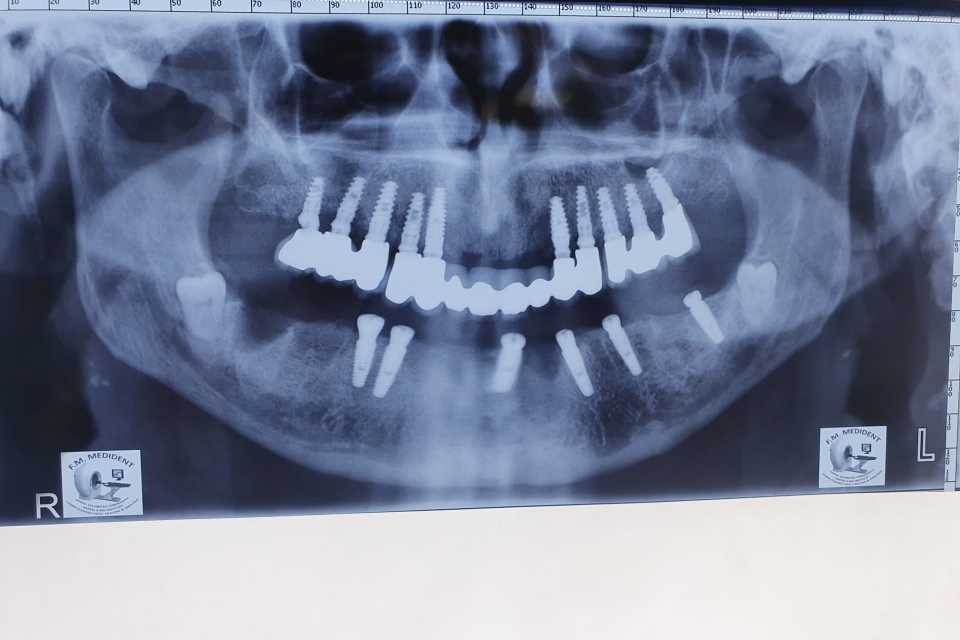

S-au inserat 10 implanturi dentare la nivel maxilar si 7 la nivel mandibular, pe baza carora s-au realizat protezari fixe metalo-cermice mandibular si ceramica pe zirconiu la nivel maxilar.

N.B. Cel de-al 7-lea implant mandibular a fost inserat la o luna distanta de la interventia initiala- defectul osos local fiind prea avansat pentru inserarea implantului in acelasi timp operator.